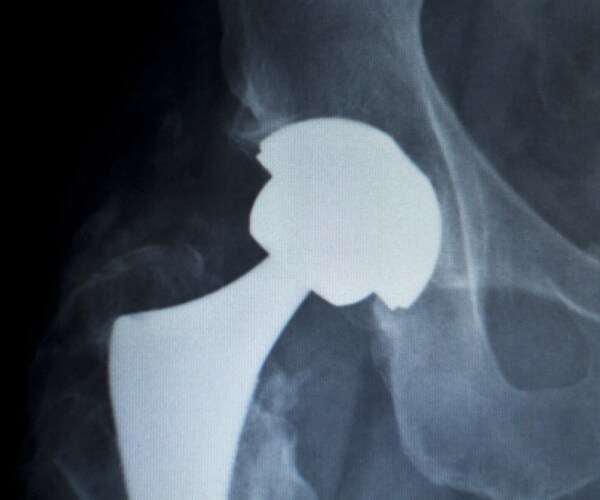

From www.istockphoto.com

Hip Titanium Implant Replacement Xray Stock Photo Download Image Now Titanium Hip Replacement Side Effects See metallosis symptoms after hip replacement surgery. But while reactions to surgical hardware and implants are rare, they do sometimes occur. In the months after her debridement and prosthesis revision, the patient continued. Hip replacement may be an option if hip pain: Soft tissue damage may lead to pain, implant loosening, device failure, and the need for revision surgery (the. Titanium Hip Replacement Side Effects.